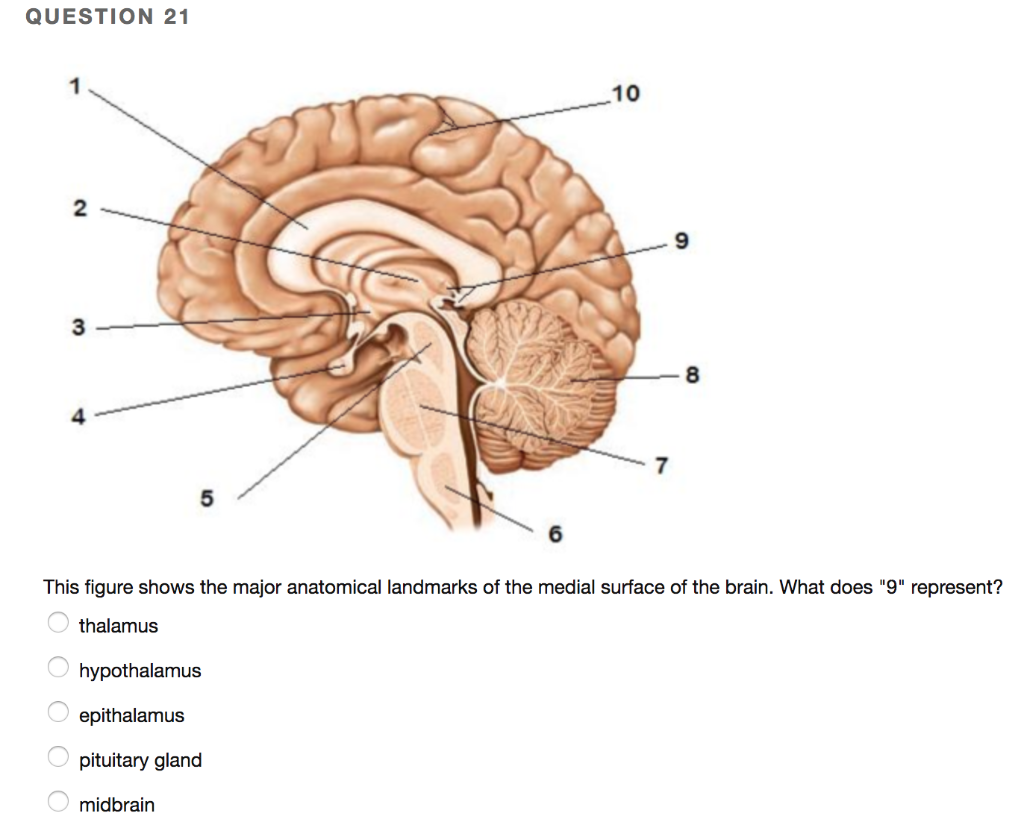

Как работает центр насыщения в гипоталамусе: визуальные иллюстрации